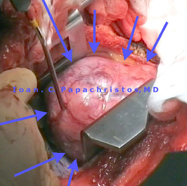

IMAGES 1-6: Type AB Thymoma, maximal dimension ~12 cm, abutting the conus arteriosus (pulmonary trunk) in a 44-yo male smoker's case (left thoracotomy through the bed of the 5th rib or the 4th intercostal space).